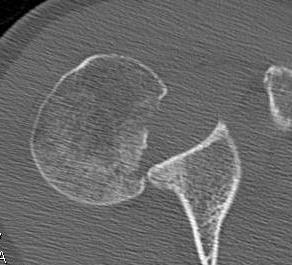

CT scan

Confirms dislocation

Reverse Hill Sachs

Humeral head defect

- caused by impaction of anterior humeral head on posterior glenoid

- intra-articular

- measured as a percentage of the articular surface

Lesser tuberosity fractures

Posterior glenoid fractures / bony bankart